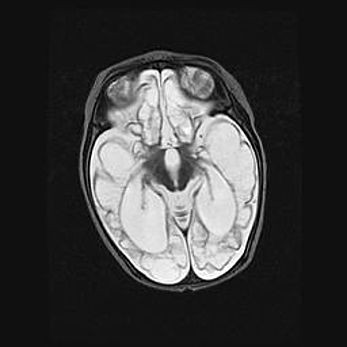

Лейкомаляция с кистозно-глиозной дегенерацией головного мозга.

Возраст: 2 месяца 25 дней

Вес: 6400 г

Окружность головы: 40 см

Срок гестации: 41 неделя

Лейкомаляцию относят к ишемически-гипоксическим повреждениям головного мозга, диагностируемым у новорожденных. При лейкомаляции в головном мозге обнаруживают очаги некроза, возникшие после тяжелой гипоксии и нарушения кровотока. В процессе морфогенеза очаги проходят три стадии: 1) развития некроза, 2) резорбции и 3) формирования глиозного рубца или кисты. Перивентрикулярная лейкомаляция (ПЛ) встречается примерно в 12% случаев среди новорожденных, обычно – у недоношенных детей, причем, частота ее зависит от массы, с которой младенец появился на свет. Наибольшее число малышей страдает лейкомаляцией, если масса при рождении 1500-2500 г.